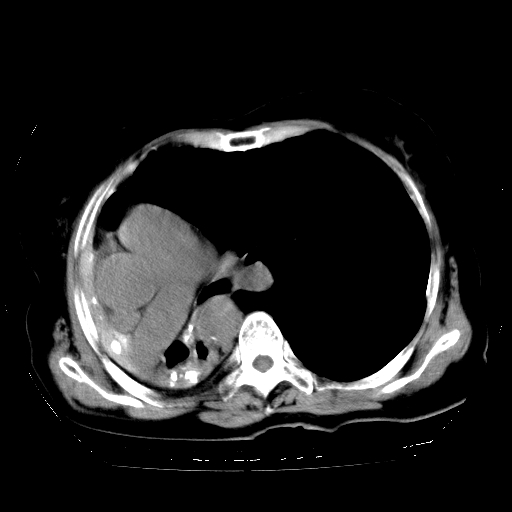

标题: CT23991:女,72岁,咳嗽、憋气一周。 [打印本页]

女,72岁,咳嗽、憋气一周,十年前曾患肺结核及胸膜结核。

1.右侧损毁肺伴胸膜钙化,2.左肺小结节灶,良性可能大,注意复查。3.肝脏左叶囊肿。4.先天性一侧肺不发育待出外(右侧胸廓无明显塌陷)。对比原片应该非常有帮助。

支持楼上,肝脏多发囊肿